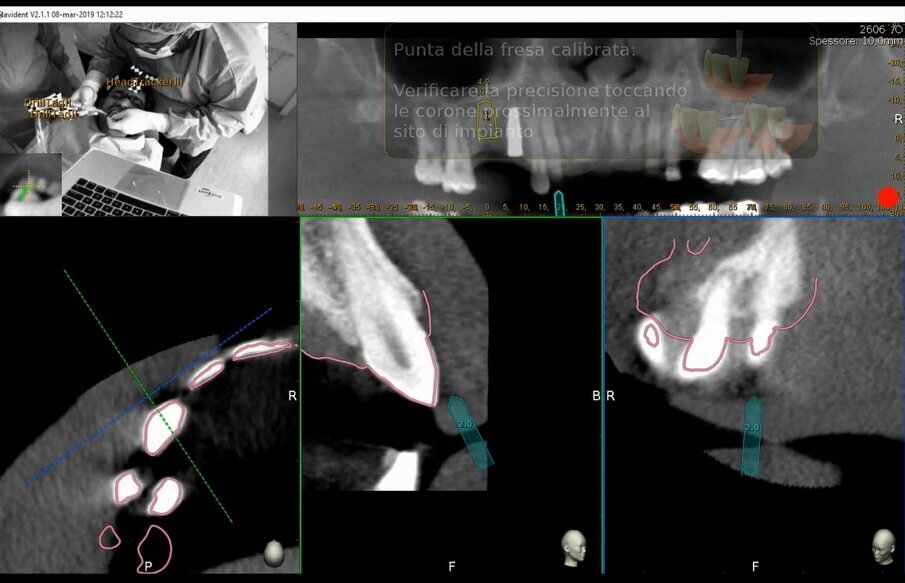

Nel protocollo Trace&Place, che presentiamo con questo caso, la superficie di registrazione a scopo interventistico sono i denti. La superficie dei denti viene letta in tempo reale mediante una scansione per tastatura attraverso un dispositivo apposito standardizzato nel sistema: Il Tracer Tool®; perché il sistema possa procedere a questa scansione è necessario anzitutto informarlo della posizione della punta del tastatore mediante una manovra di calibrazione. Si scelgono quindi tre o più denti dal modello 3D ricavati dai dati TAC del paziente indicando un preciso punto facilmente identificabile da cui iniziare la scansione (ad esempio la punta di una cuspide o una particolarità anatomica unica come una fossetta di usura). Se ne tastano le superfici con movimenti rapidi per lo più di traslazione dello strumento; un feedback sonoro segnala l’inizio, dall’esecuzione e dal termine di ogni scansione. La scelta dei denti non può essere causale: essi devono essere sufficientemente distanti e distribuiti nell’arcata per rappresentare un solido abbastanza descrittivo della regione clinica da approcciare. Ciò è quanto veniva effettuato nel caso in questione (Figg. 6a-6d).

Figg. 6a-6d - Tracciatura della superficie di riferimento in tempo reale. a) Calibrazione del tastatore; b) Selezione dei denti e dei punti di partenza della scansione per tastatura; c) Fasi di scansione (tracer registration); d) Dettaglio clinico della procedura di tracer registration.

La precisione della chirurgia guidata ha una media ed una deviazione standard; la precisione di una specifica chirurgia; del gesto chirurgico nello specifico paziente non può essere nota a priori e può essere valutata solo postintervento. La chirurgia navigata è sotto controllo continuo. Anzitutto in fase di inizializzazione del sistema viene richiesto di verificare la presenza di artefatti di movimento nella TAC. Pur essendo lontani da un algoritmo di riconoscimento automatico di TAC “Mosse” almeno è un avviso che richiede una responsabilizzazione del clinico operatore invitato a controllare l’esattezza dell’esame; in nessuno dei sistemi di chirurgia guidata di mia conoscenza, dai più ai meno blasonati, è presente un tale cruciale passaggio. Dopo ogni cambio fresa, inoltre, il sistema chiede di calibrare la posizione della punta della fresa ed una verifica di accuratezza (accuracy check) che consiste nel toccare superfici perfettamente evidenziabili nella TAC vicine il sito di intervento a verificare con quale precisione sta avvenendo la lettura (Figg. 13a-13c). Ovvio che il sistema non riconosce il “Cambio fresa” ma un periodo di inattività che può essere impostato secondo le esigenze personali così come si può decidere di disabilitarlo nelle impostazioni del sistema, sebbene si tratti di una scelta poco raccomandabile.

Figg. 13a-13c - Verifica di accuratezza. a) Verifica di accuratezza del Tracer dopo tastatura; b, c) Verifica di accuratezza della fresa prima della fresatura.